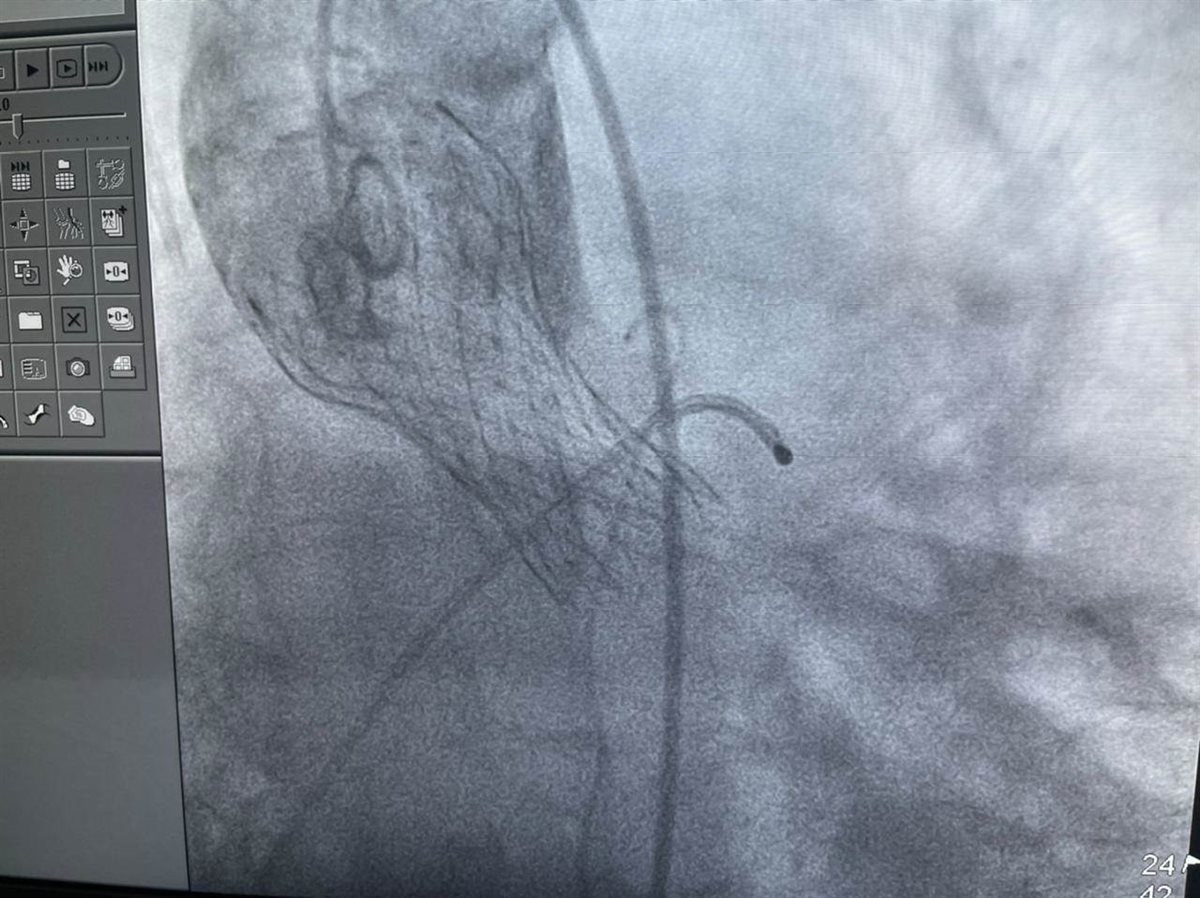

وأشارت الهيئة، إلى أن تقنية “التافي” هي أحدث التقنيات المستخدمة لعلاج أمراض القلب، ومن أحدث ما توصل إليه العلم في عمليات استبدال الصمام الأورطي، والتي تعني استبدال الصمام من دون شقّ منطقة الصدر، وذلك عن طريق القسطرة دون اللجوء إلى الجراحات التقليدية كالتدخل الجراحي في جراحات القلب المفتوح.

وأضافت، أنه تم إجراء عملية استبدال الصمام الأورطي للمريضة عن طريق تقنية التافي، حيث كانت تعاني من ضيق شديد بالصمام إضافة إلى إصابتها بمرض السكري والسمنة المفرطة وارتفاع ضغط الدم، والذي أدى إلى صعوبة التعامل مع الحالة المرضية جراحيًا وعدم اللجوء إلى الجراحات التقليدية واستبدالها بتقنية التافي حفاظًا على حياة المريضة.